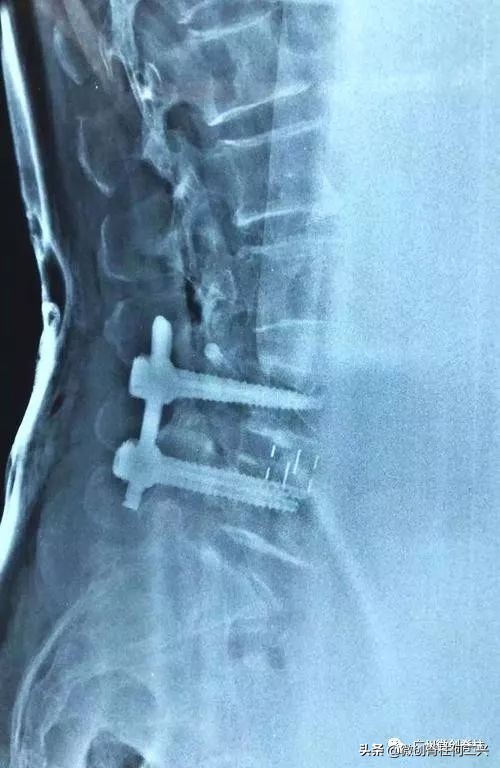

今天就来整理一下,全内窥镜下腰椎融合术后注意事项。

3、术后一个月门诊复查,术后每3个月再复查腰椎x光、CT

7、每年复诊1次,拍照x光片和ct,了解融合是否完成。一般2年半到3年大部分患者都会融合。